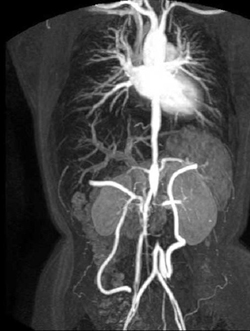

Il progetto europeo CROSSGRID ha sviluppato un nuovo sistema interattivo basato su Grid per la visualizzazione delle procedure chirurgiche.

È stato sviluppato un prototipo di ambiente problem-solving (PSE) per la chirurgia vascolare virtuale. È stata sviluppata una serie di risorse hardware e software disponibili tramite l'infrastruttura CrossGrid. Queste risorse sono state usate per costruire un ambiente specifico per aiutare chirurghi vascolari e radiologi interventisti nel processo decisionale preoperatorio. I risultati dell'equipe sono stati l'accesso sicuro alla Grid, la scoperta e la registrazione del nodo, il trasferimento dati con Grid, l'inizializzazione dell'applicazione, la segmentazione dei dati medici, la visualizzazione dei dati segmentati e la creazione di mesh computazionali. Hanno anche ottenuto un avvio sicuro del lavoro, un flusso ematico distribuito e la creazione di bypass. L'applicazione medica per la ricostruzione vascolare è stata incorporata nella Grid. È stato usato un deposito di immagini mediche a Leiden per reperire i dati per gli esperimenti. Le risorse della Grid sono state usate per simulare il flusso ematico del paziente. Un efficiente solutore mesoscopico di emodinamica computazionale per le simulazioni del flusso ematico era basato sugli automi cellulari paralleli. Il flusso pulsatile Newtoniano è stato simulato in un tubo 3D rigido dritto. Il volume di simulazione è stato diviso in un numero di sotto-volumi per consentire l'esecuzione in parallelo e ogni sotto-volume è stato elaborato contemporaneamente. Uno straordinario sistema di realtà virtuale da tavolo è stato sviluppato per garantire la facilità d'uso. Viene usato come front end per l'interazione-visualizzazione per la persona che gestisce il sistema tramite Grid. Gli utenti finali erano in grado di interagire con il sistema tramite un'interfaccia multimodale. Quest'ultima ha integrato modalità input naturali che si possono gestire con la voce, con i movimenti delle mani e con la manipolazione di oggetti 3D. Il sistema è stato chiamato Virtual Operating Theatre. L'operatore fa la parte del chirurgo vascolare, trattando i disturbi vascolari su un paziente virtuale simulato.